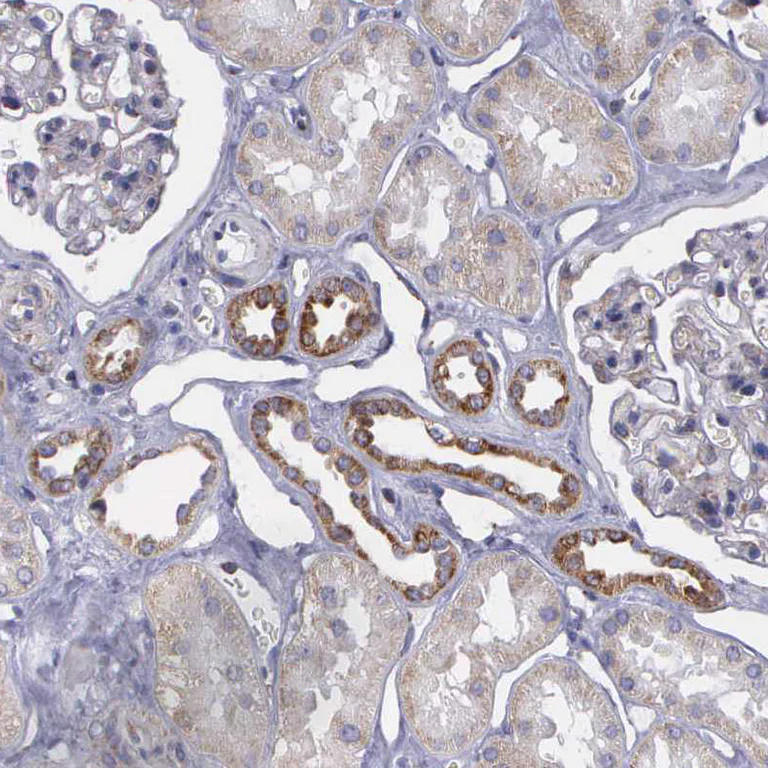

Immunohistochemistry (Formalin/PFA-fixed paraffin-embedded sections) - Anti-SYNJ2BP antibody - N-terminal (AB224217)

ab224217 (1 : 500 dilution) staining SYNJ2BP of human paraffin-embedded kidney tissue by immunohistochemcial analysis shows moderate granular cytoplasmic positivity in distal tubules cells.